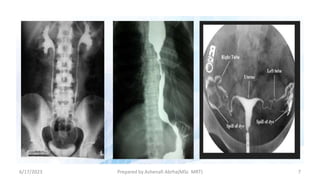

Without CM With CM

B

A

6/17/2023 Prepared by Ashenafi Abrha(MSc MRT) 7

Effect of Contrastmedia 6/17/2023 Prepared by Ashenafi Abrha(MSc MRT) 6 Without CM With CM B A